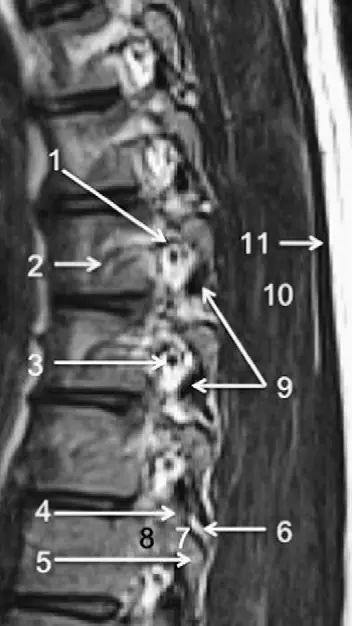

图 3 腰椎矢状位 T1WI 序列成像:1,脊髓;2,脊髓圆锥;3,马尾;4,蛛网膜下腔;5,硬膜外脂肪;6,黄韧带;7,棘间韧带;8,棘上韧带;9,椎体静脉丛;10,硬膜外静脉丛;11,硬膜外脂肪;12 主动脉

图 5 腰椎旁矢状位 T1WI 序列成像:1,腰静脉;2,腰动脉;3,椎间孔静脉;4,脊神经节后根;5,椎间孔静脉;6,关节面;7,多裂肌;8,竖脊肌群;9,胸腰筋膜,后层